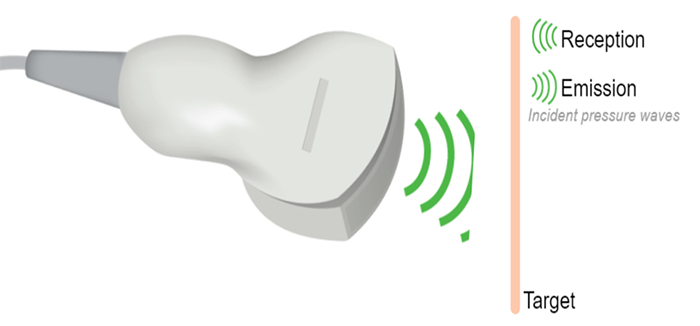

It is known that the crystals in the ultrasonic probe change shape, and emit ultrasonic waves when stimulated by an electrical current. These sound waves reflect off the surface of the body and collide with quartz crystals, which then produce an electrical current.

General Aspect

A common approach, any ultrasound transducer has the same role as an ear or mouth; it sends and receives ultrasound waves. The transducer is the hand part of the machine, responsible for the ultrasound production and detection. It converts the electrical energy into mechanical energy and vice versa, based on the piezoelectric effect.